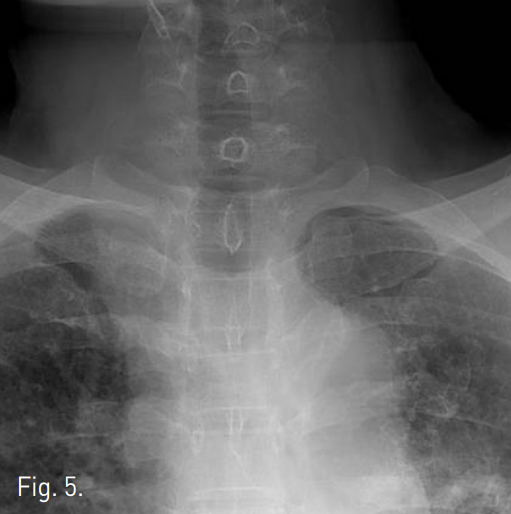

Supine position에서 국소마취 후 bronchoscopic guidance하에 0.035 inch stiff guide wire를 segmental bronchus level 이하까지 전진 시킨 후 5F sizing catheter를 삽입 후 병변의 위치 및 정도를 bronchography를 통하여 확인함. 병변을 확인한 후 15mm 및 20mm x 60mm balloon catheter를 통하여 dilatation을 시행함(Fig. 3). 시술 직후 bronchoscopy에서 web이 찢어지고 내경이 상당히 넓어져 있음(Fig. 4). 한달 후의 투시영상에서 잘 넓어져 있는 상태가 유지됨(Fig. 5).

Fig. 4

Immediately after balloon dilation, luminal stenosis much improved.